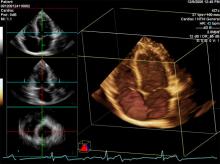

With last year’s U.S. Food and Drug Administration approval of transcatheter aortic valve replacement (TAVR) and increasingly complex cath lab and hybrid operating room (OR) interventions, ultrasound is playing an increasing role in procedural guidance. This is especially true for use of 3-D/4-D transesophageal echo (TEE), which enables the more precise surgical-view visualization required for structural heart procedures, such as atrial septal defect (ASD) occluder and MitraClip deployments. These repairs would otherwise be extremely difficult to accomplish using fluoroscopy alone.

Three big trends were seen in cardiovascular ultrasound during the American Society of Echocardiography (ASE) 2012 meeting. Malissa Wood, M.D., co-director of the Women's Center at Mass General Hospital, Boston, and chair of the ASE Public Relations Committee, explains these trends. The biggest is the expanding use of ultrasound and transesophageal echo (TEE) in the cath lab and hybrid OR for structural heart procedural navigation. Other trends include use of pocket ultrasound and new software advances to simlify and reduce the time it takes to use 3-D echo and make quantifications. For more information: www.dicardiology.com/article/ultrasound-sees-increasing-use-interventional-procedures

Enhanced features on the Philips EPIQ CVx ultrasound system provide a next level photorealistic 3D rendering, making it easy for users to interpret what they are seeing. The TrueVue feature enhances the sense of depth and space, producing images that appear natural and realistic to the human eye.